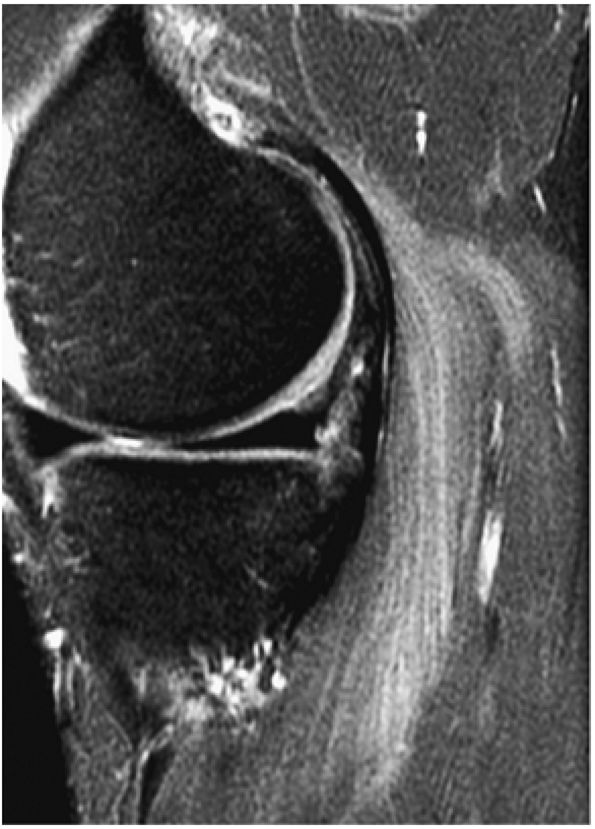

FIGURE 5.1 ● Visualization of tibiotalar articular surfaces using a coronal FS PD FSE sequence. Separation of the tibial and talar chondral surfaces is important in characterizing osteochondral lesions.